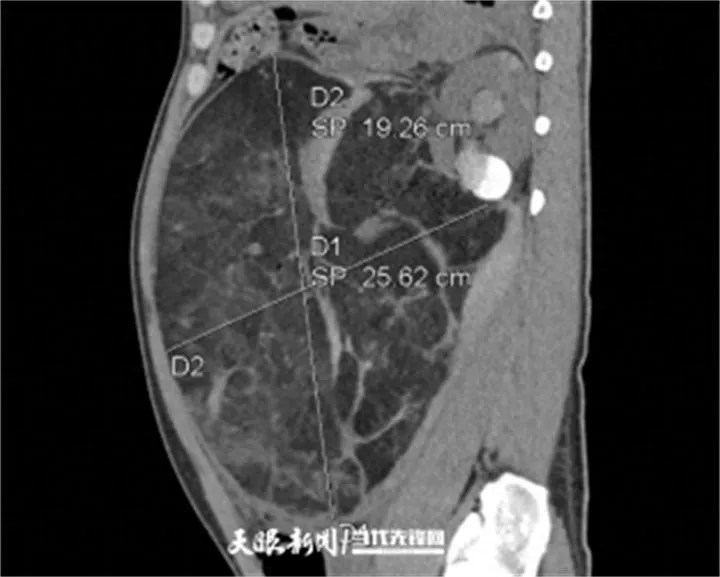

近日,因长期疏于体检,张先生突发剧烈腹痛并伴头晕心慌,被紧急送至贵州医科大学附属医院。急诊 CT 检查结果令人震惊:其左肾内长有一个体积达 27cm×25cm 的巨大错构瘤,并且已经破裂出血。

这个瘤体大小堪比一个篮球,巨大的占位已严重压迫周围脏器。更危急的是,肿瘤破裂导致大出血,患者血压持续下降、心率加快,濒临失血性休克,生命危在旦夕。

医讯网:33 岁男子腹痛就医,竟查出篮球大肾错构瘤破裂大出血!急诊 CT 显示,患者左肾巨大错构瘤已破裂出血。